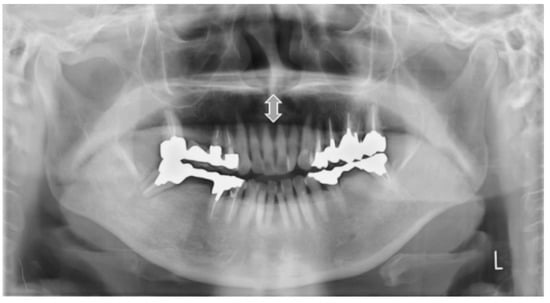

2.4.1. Vertical Hyoid Bone Position

Figure 1 illustrates the evaluation of the vertical position of the hyoid bone and shows sample images. This method of measurement was as specified in Ito et al. [9]. Figure 2 shows sample images.

Figure 1.

Vertical hyoid bone position. Mandibular border line was defined as a line that moves virtual line which is connecting the both side of mandibular angles, in parallel along the center line and attach to the lowest point of the mandibular inferior edge. An evaluation was conducted of the extent to which the hyoid body and greater horn appeared in the upper area from the mandibular border line.

Figure 2.

Sample images of vertical hyoid bone position. Arrow shows the hyoid bone. On Type 0, hyoid bone is invisible.

Two landmarks were defined, as follows:

- The bilateral mandible line: A simulated line connecting the right and left sides of the angles of the mandible.

- The mandibular border line: The line that moved the bilateral mandibular line parallel to the lowest point of the lower border of the mandible.

An evaluation was conducted of the extent to which the hyoid body and greater horn appeared in the upper area from the mandibular border line. The following six groups were categorized:

Type 0: The hyoid bone could not be observed in the upper area from the mandibular border line;

Type 1: Only the greater horn was observed in the upper area from the mandibular border line;

Type 2: A less than half of the hyoid body was observed in the upper area from the mandibular border line;

Type 3: More than half and less than whole of the hyoid body was observed in the upper area from the mandibular border line;

Type 4: All of the hyoid body was observed in the upper area from the mandibular border line;

Type 5: The hyoid body overlapped with the mandible bone.

On the right and left sides, if the vertical position of the hyoid bone was different, the lower position side was recorded.